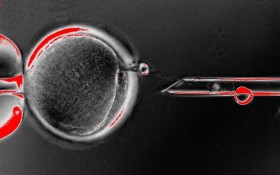

Today marks the start of a collaboration between biologists at RIKEN Center for Developmental Biology and a hospital in Kobe, Japan. Together, they hope to cure age-related macular degeneration by transplanting sheets of retina grown using patient derived, induced pluripotent stem cells.